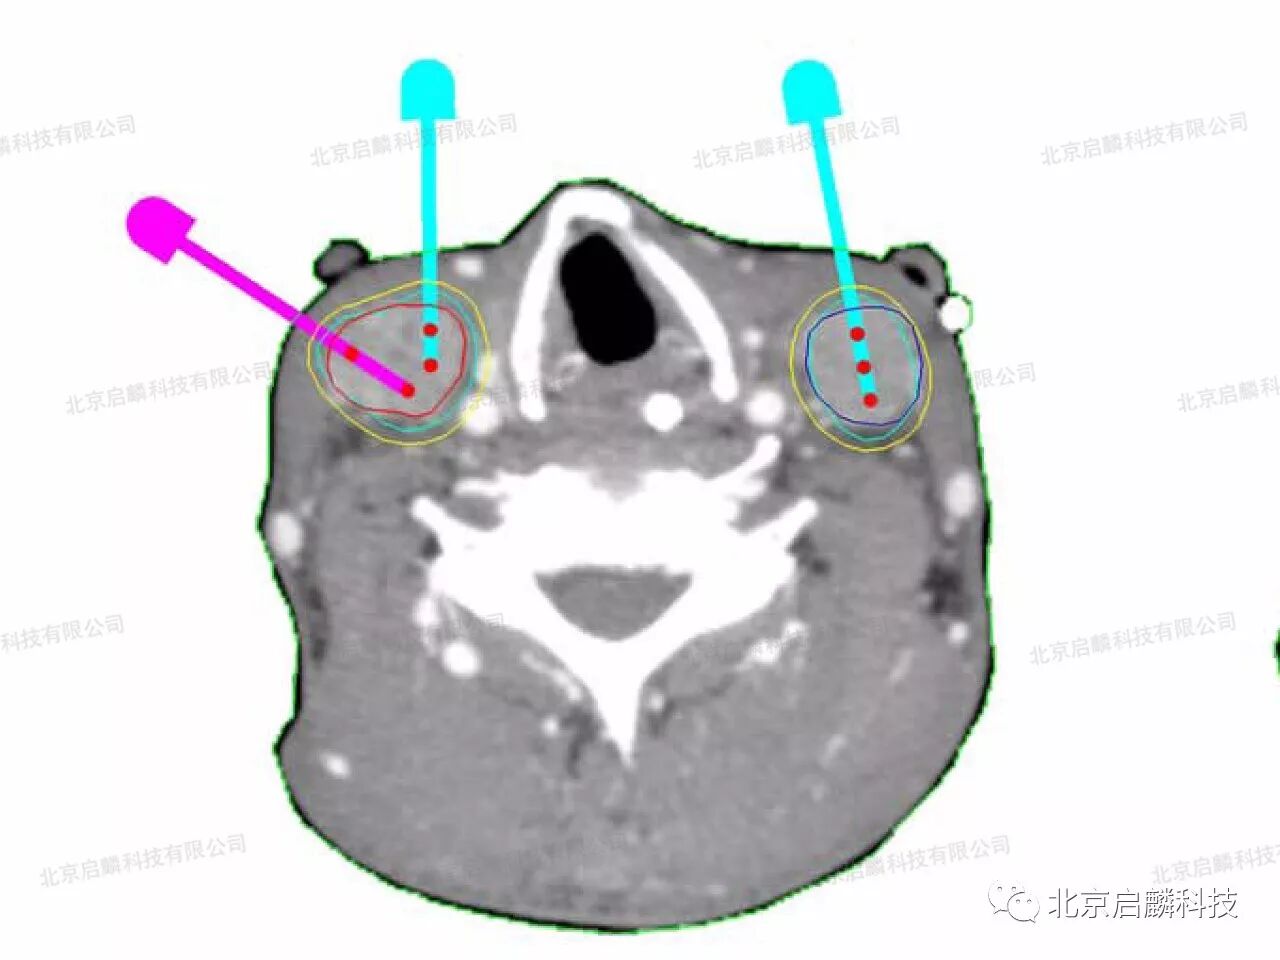

在北京启麟科技有限公司的帮助下,术前患者进行了CT检查、肿瘤位置体表定位;制定TPS治疗计划;打印3D微创导向模板,经过核医学科粒子治疗团队的医生、技师、护士密切配合下,陈志军主任和王文俊医生在CT引导及3D微创导向模板辅助下同时进行双侧颈淋巴结转移癌碘-125粒子植入术,经校准模板后所有穿刺针一次植入到位,成功完成治疗。

3D微创导向模板引导下的精准施术

3D微创导向模板由北京启麟科技提供

术前设计进针路线和粒子规划